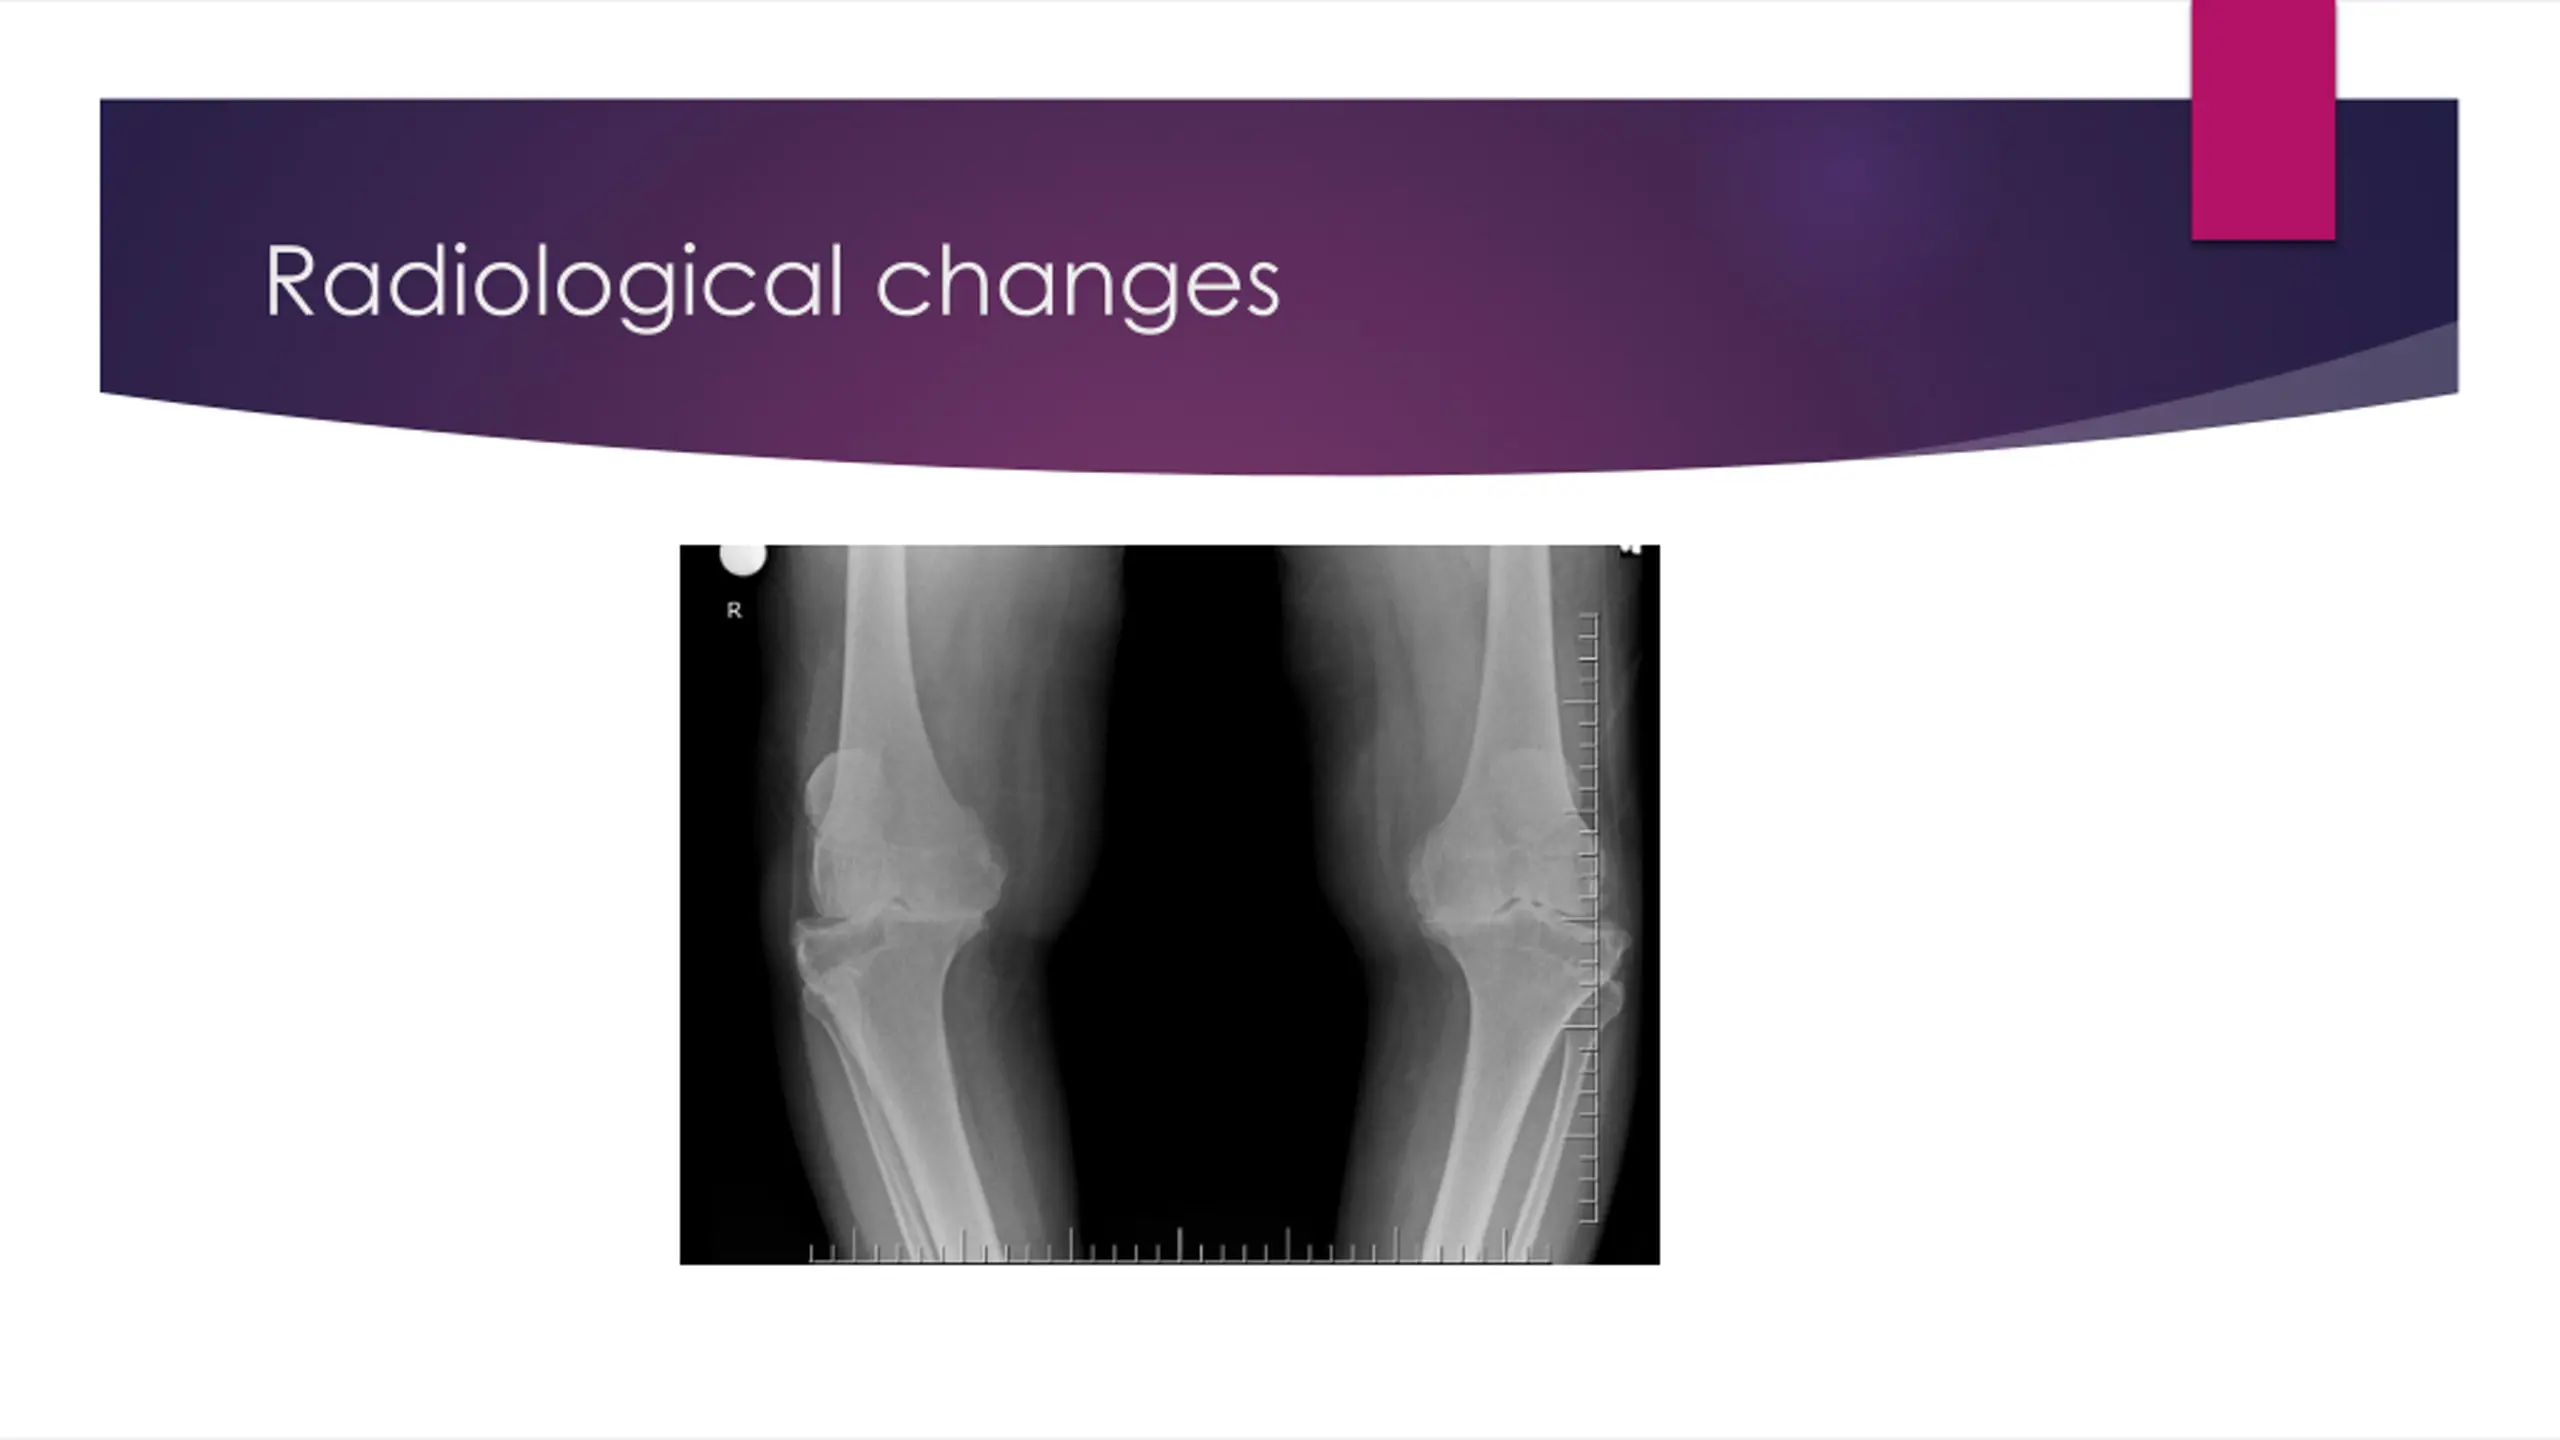

OA - Definition Heterogeneous group of conditions resulting in common histopathologic and radiologic changes involving Entire joint organ, including: the articular cartilage the subchondral bone and the synovium.

Pathogenesis Swelling of the cartilage usually occurs the level of proteoglycans eventually drops very low, the cartilage softens and lose elasticity and compromising joint surface integrity. Flaking and fibrillations (vertical clefts) develop along on the surface of an osteoarthritic joint. Over time, the loss of cartilage results in loss of joint space. a greater loss of joint space occurs at those areas experiencing the highest loads.

Bone changes Bone denuded of its protective cartilage continues to articulate with the opposing surface. Eventually, the increasing stresses exceed the biomechanical yield strength of the bone. The subchondral bone responds with vascular invasion and increased cellularity, becoming thickened and dense (a process known as eburnation) at areas of pressure.

Bone changes subchondral bone undergo cystic degeneration. Osteoarthritic cysts are also referred to as subchondral cysts, pseudocysts, or geodes and may range from 2 to 20 mm in diameter. Osteoarthritic cysts in the acetabulum are termed Egger cysts.

Joint changes vascularization of subchondral marrow, osseous metaplasia of synovial connective tissue, and ossifying cartilaginous protrusions lead to irregular outgrowth of new bone (osteophytes). Fragmentation of these osteophytes or of the articular cartilage itself results in the presence of intra-articular loose bodies (joint mice).